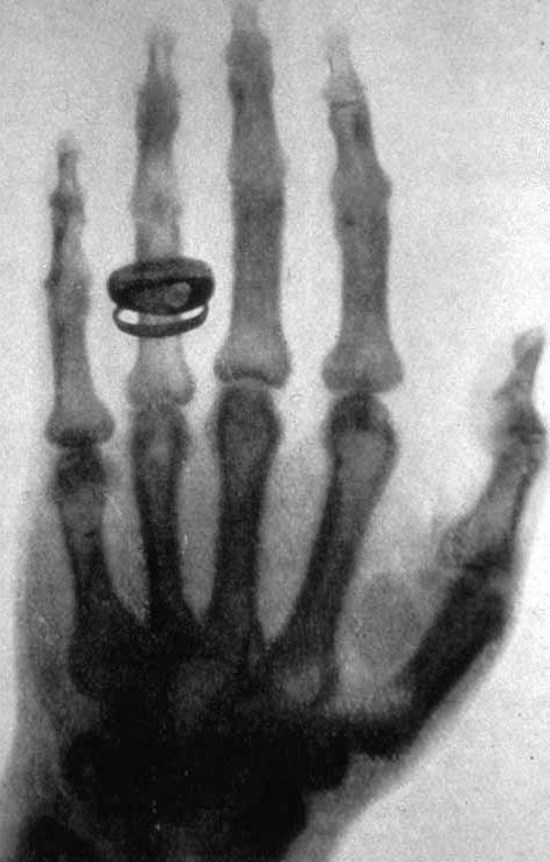

Several days before Christmas in the same year, Röntgen used

his cathode-ray apparatus to take a radiographic image of his

wife Bertha's hand. Several days after Christmas, he submitted

an article describing his findings, along with the picture, to

a scholarly journal. The article excited widespread interest,

the picture became famous, and Röntgen won a Nobel prize in

1901. He named his mysterious findings X-rays, but much of the

world called them Röntgen rays. Their diagnostic potential was

recognized immediately: in 1896 a number of physicians and

surgeons used the new rays to look inside patients' bodies,

and at least two medical handbooks, Practical Radiography

and The X-ray, or, Photography of the Invisible and its

Value in Surgery, were published.